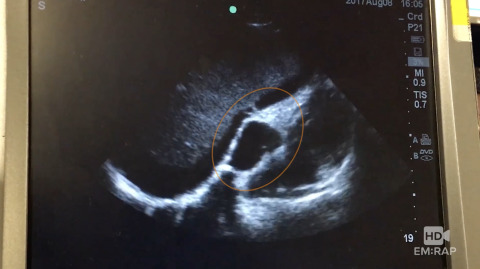

Saline Flush to Confirm Central Line Placement

Dr. Jess Mason presents a technique to confirm that a central line is venous, not arterial, using ultrasound a saline flush. Procedure performed with Dr. Eileen Shu.

1 chapterAugust 2017